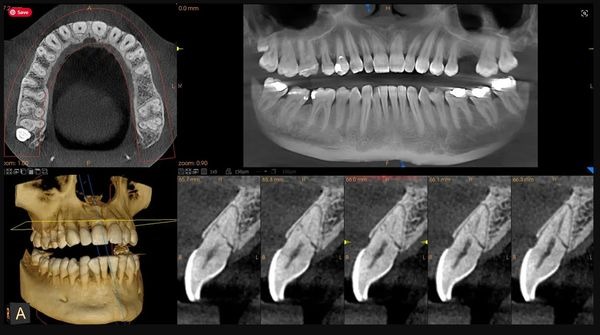

Cone Beam or 3D X-Ray

A Cone Beam CT (CBCT) scan, also called a 3D dental x-ray, is an advanced imaging technology that provides a three-dimensional view of your teeth, jaws, sinuses, and surrounding structures. Unlike traditional 2D x-rays, CBCT captures the full anatomy in high detail, giving your dentist or oral surgeon the most accurate information for diagnosis and treatment planning.

Uses of Cone Beam 3D X-Rays

CBCT scans are especially useful for:

- Planning dental implants with precise measurements of bone and nerve locations

- Evaluating impacted teeth, including wisdom teeth

- Assessing jaw tumors, cysts, or other abnormalities

- Diagnosing complex dental or jaw conditions

- Supporting orthodontic planning and airway assessments

- Detecting root fractures or complex root canal anatomy

Advantages of Cone Beam 3D Imaging

- Comprehensive, three-dimensional view: Provides a complete picture of your oral anatomy, revealing details that 2D x-rays may miss.

- Precise treatment planning: Helps your dentist place implants or perform surgery with greater accuracy, improving outcomes and reducing risks.

- Low radiation for 3D imaging: Modern CBCT units are designed to minimize exposure while delivering detailed images.

- Quick and non-invasive: The scan typically takes less than a minute, and you remain seated or standing during the process.

- Improves communication: 3D images allow your dentist to explain findings clearly, helping you understand your treatment options.